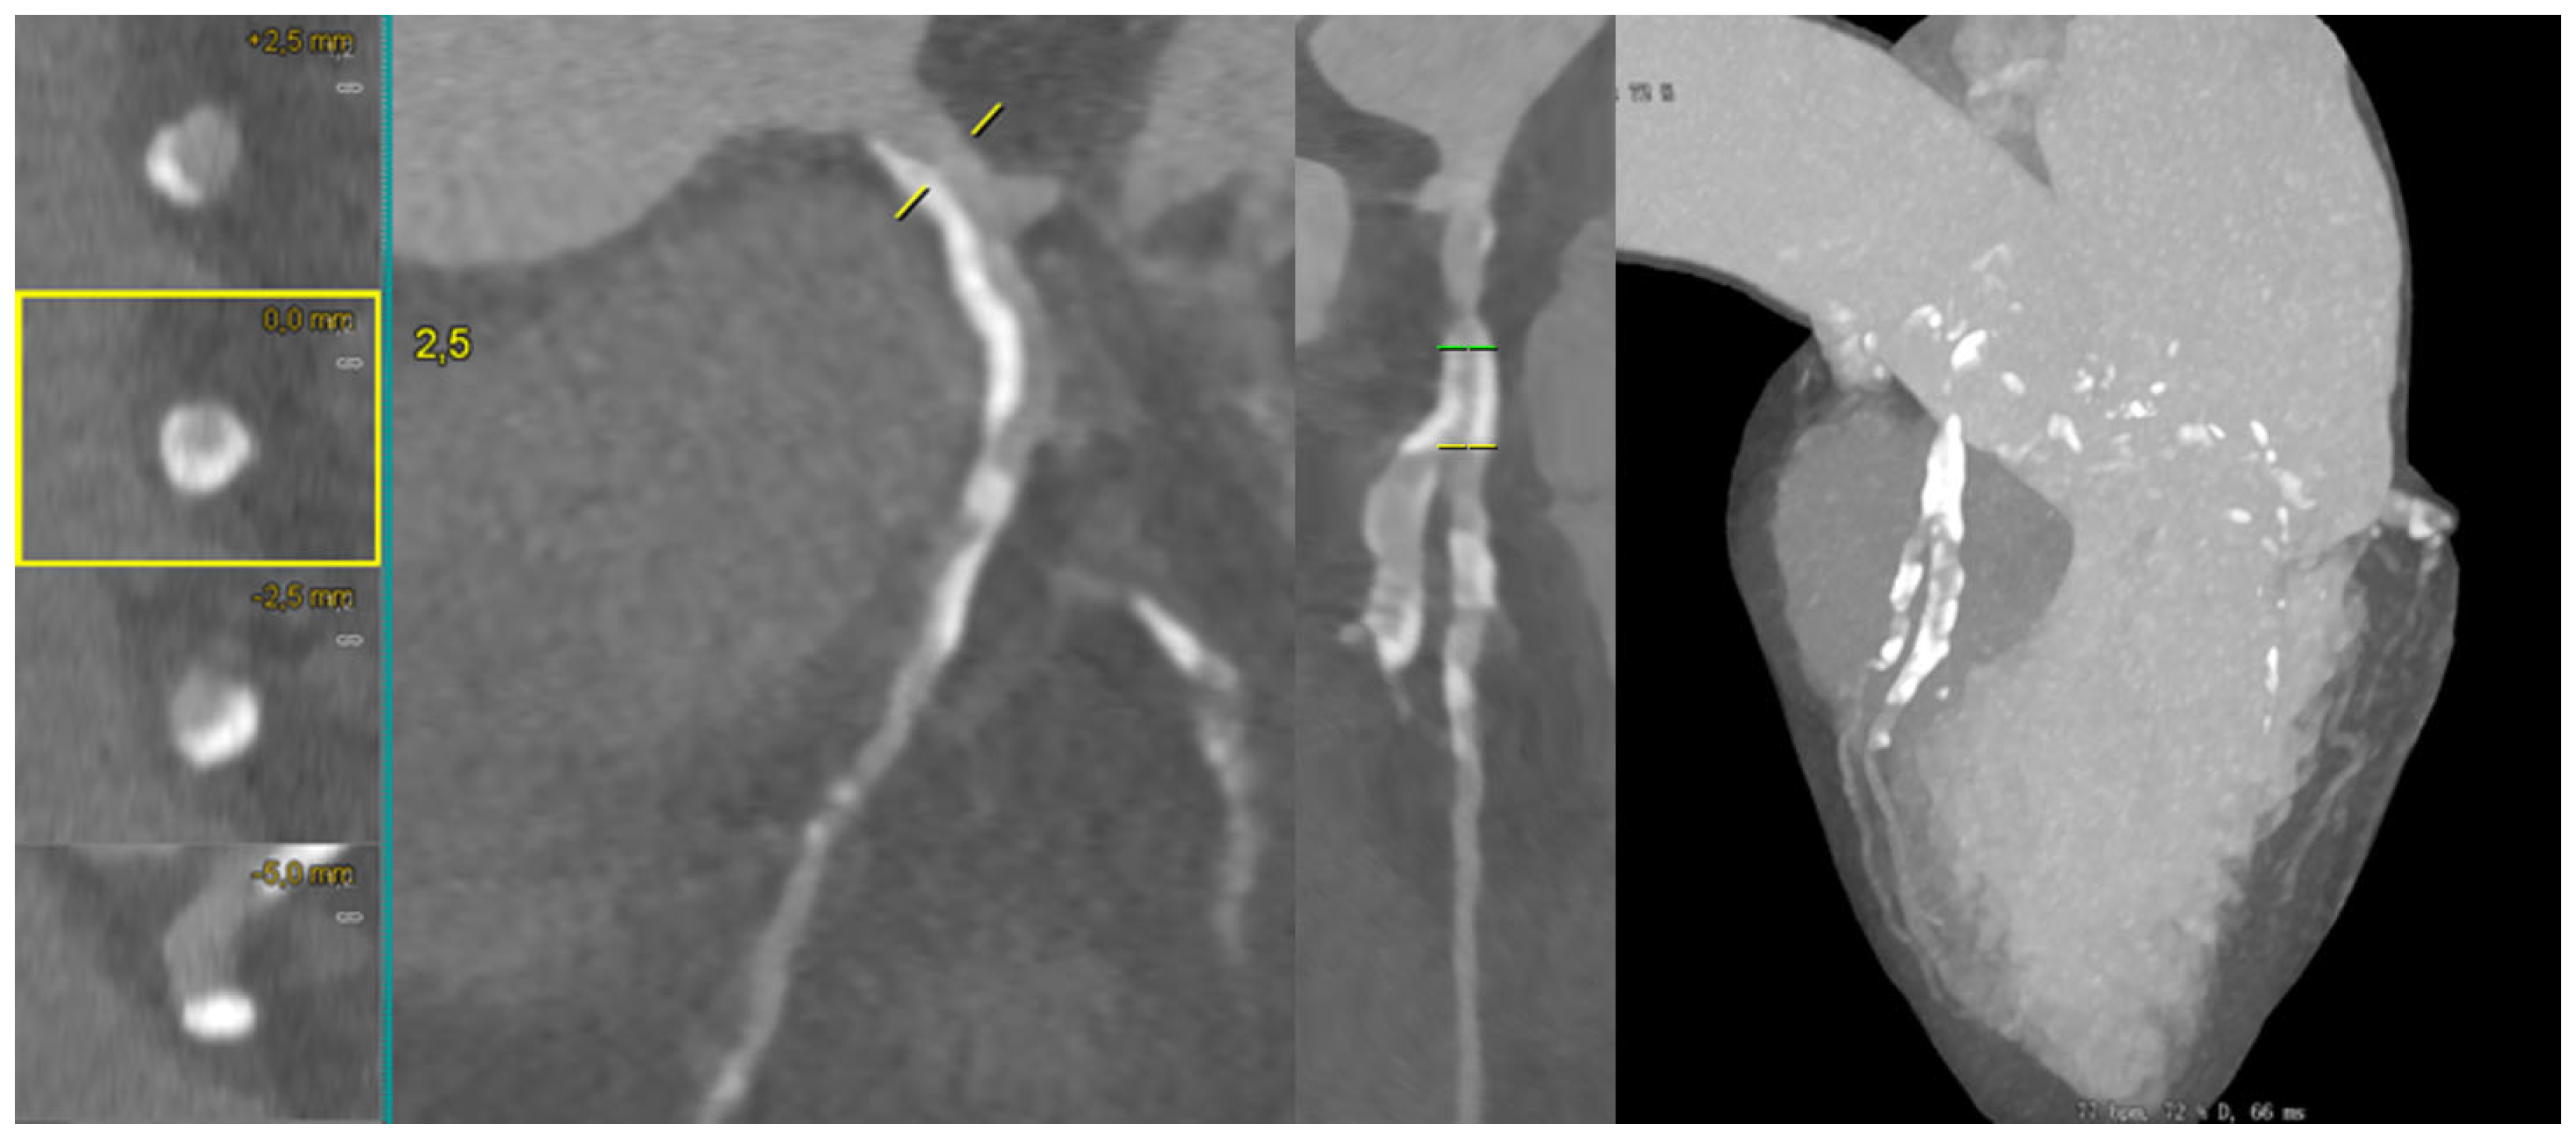

Figure 6 illustrates a calcified LAD–D1 bifurcation lesion, where long-axis and cross-sectional MPR views demonstrate semi-circumferential calcium distribution, allowing for the semiquantitative assessment of the calcific burden. The complementary MIP reconstruction highlights the extent of calcification across the bifurcation segment.

Figure 6.

CCTA evaluation of a heavily calcified LAD–D1 bifurcation lesion. Long-axis MPR reconstruction of the left anterior descending artery (LAD) shows an extended calcified plaque involving the proximal and mid segments, with an additional MPR view illustrating severe calcification across the LAD–first diagonal (D1) bifurcation. The MIP CCTA reconstruction further highlights the complex and heavily calcified morphology of the lesion. Abbreviations: LAD, left anterior descending; D1, first diagonal; MPR, multiplanar reconstruction; MIP, maximum intensity projection; CCTA, coronary computed tomography angiography.